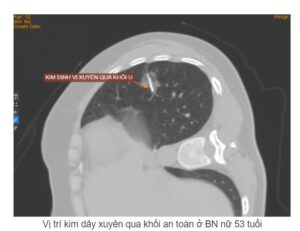

Định vị khối u phổi bằng kim dây dưới hướng dẫn CLVT trước phẫu thuật là phương pháp mới, hiện đại, giúp tìm chính xác vị trí khối u phổi trước khi điều trị phẫu thuật. Dưới hướng dẫn của kim định vị, phẫu thuật viên dễ dàng cắt bỏ khối u phổi tối thiểu nhất, hạn chế tai biến và tàn tật, đem lại hiệu quả điều trị cao cho bệnh nhân ung thư phổi.

Trong quá trình chuẩn bị trước phẫu thuật đối với một bệnh nhân có khối u ở phổi, việc định vị khối u trước phẫu thuật là rất cần thiết, đặc biệt là các khối u nhỏ, khi các Phẫu thuật viên (PTV) muốn cắt bỏ tối thiểu, giúp giữ lại gần hoàn toàn chức năng phổi, hạn chế tai biến và tàn tật, rút ngắn thời gian mổ và hồi sức cũng như chăm sóc điều trị hậu phẫu. Tuy nhiên, trong quá trình phẫu thuật, PTV cần đánh xẹp phổi thì việc tìm vị trí khối u là rất khó khăn. Vì vậy trước đây thường phẫu thuật rộng, cắt bỏ cả thùy phổi hoặc toàn bộ phổi có tổn thương. Tuy nhiên, ngày nay nhờ có phương pháp sử dụng kim định vị khối u trước phẫu thuật mà PTV dễ dàng tìm thấy khối u và cắt bỏ nhanh chóng, chính xác và an toàn. Định vị khối u bằng kim dây trước phẫu thuật dưới hướng dẫn CLVT là kỹ thuật sử dụng kim dây thép Bard® DuaLok™ Breast Localization Wire, đây là một loại kim thường dùng định vị các khối u ở vú giúp sinh thiết và phẫu thuật cắt bỏ.

• Sau gây tê 2 phút thì tiến hành đặt kim dây, kim được đặt trước hoặc sau khối u tùy khối u nằm gần hay xa thành ngực, kiểm tra lại bằng CLVT xem đã chính xác chưa